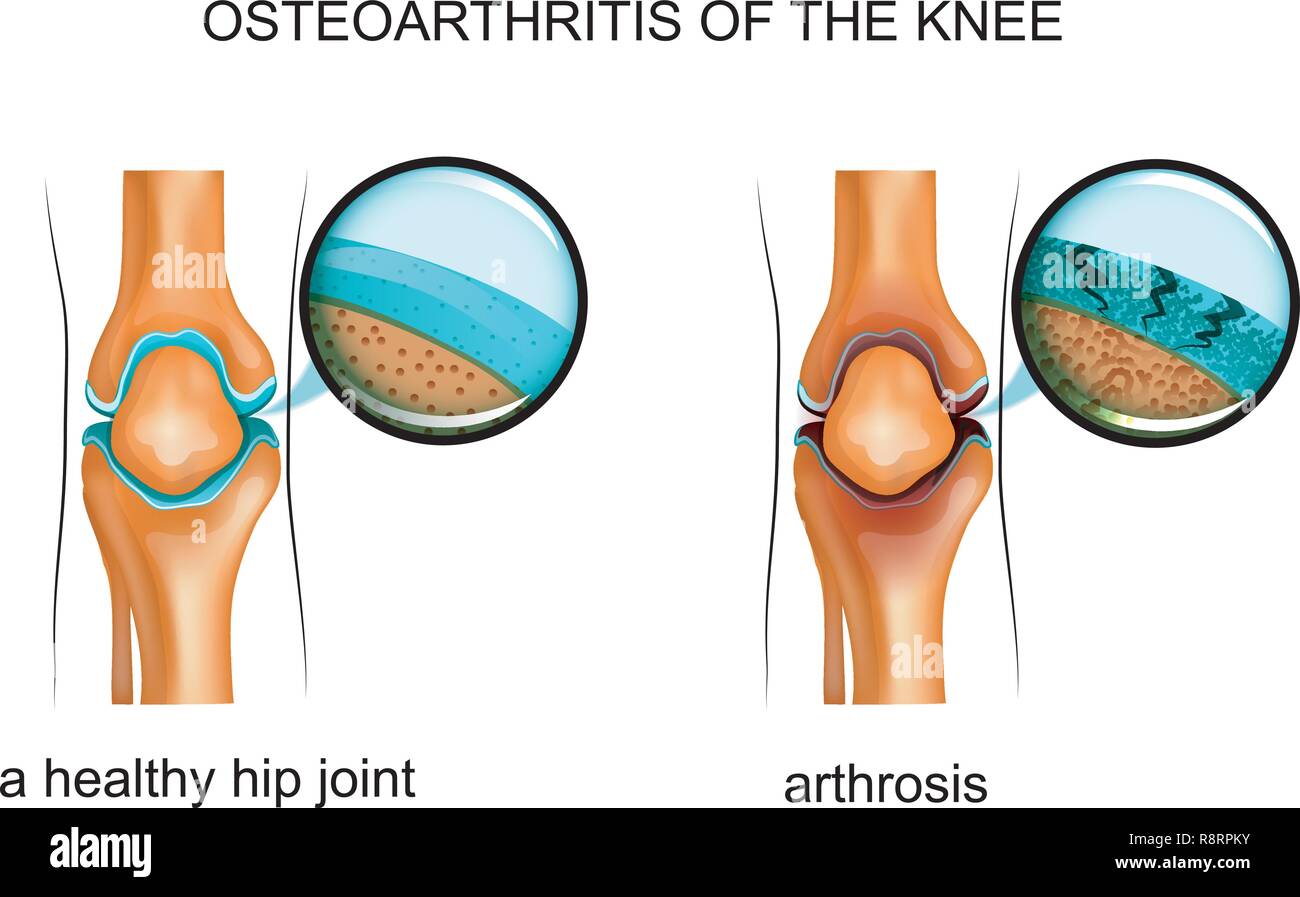

vector illustration of osteoarthritis of the knee Stock Vectorhttps://www.alamy.com/image-license-details/?v=1https://www.alamy.com/vector-illustration-of-osteoarthritis-of-the-knee-image229174735.html

vector illustration of osteoarthritis of the knee Stock Vectorhttps://www.alamy.com/image-license-details/?v=1https://www.alamy.com/vector-illustration-of-osteoarthritis-of-the-knee-image229174735.htmlRFR8RPKY–vector illustration of osteoarthritis of the knee